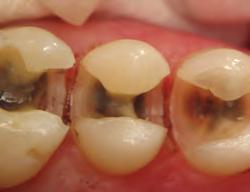

• Large food trap above

• Fails to restore proximal anatomy

• Thin contact at the marginal ridge

• Likelihood of fracture, occlusal interference, recurrent caries, and periodontal disease

• User-friendly system

• Natural contours

• Tight, anatomically correct contact points at correct height of contour

DISTO-OCCLUSAL CLINICAL CASE